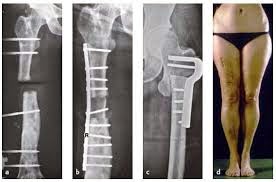

This method of immediate limb

lengthening would extend the size in length in cases of height. That could be

by administration of stimulation of growth or distraction osteogenesis.